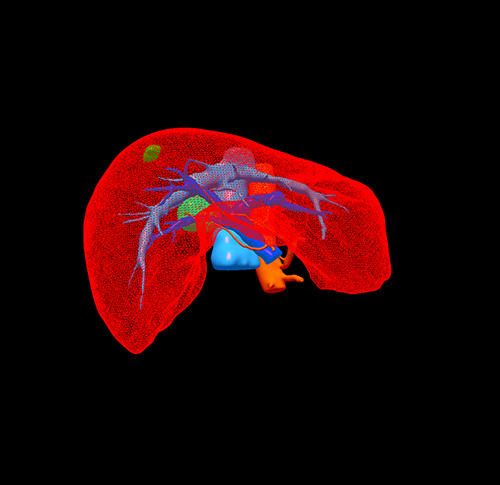

S678肝癌 ---腹腔镜右半肝切除